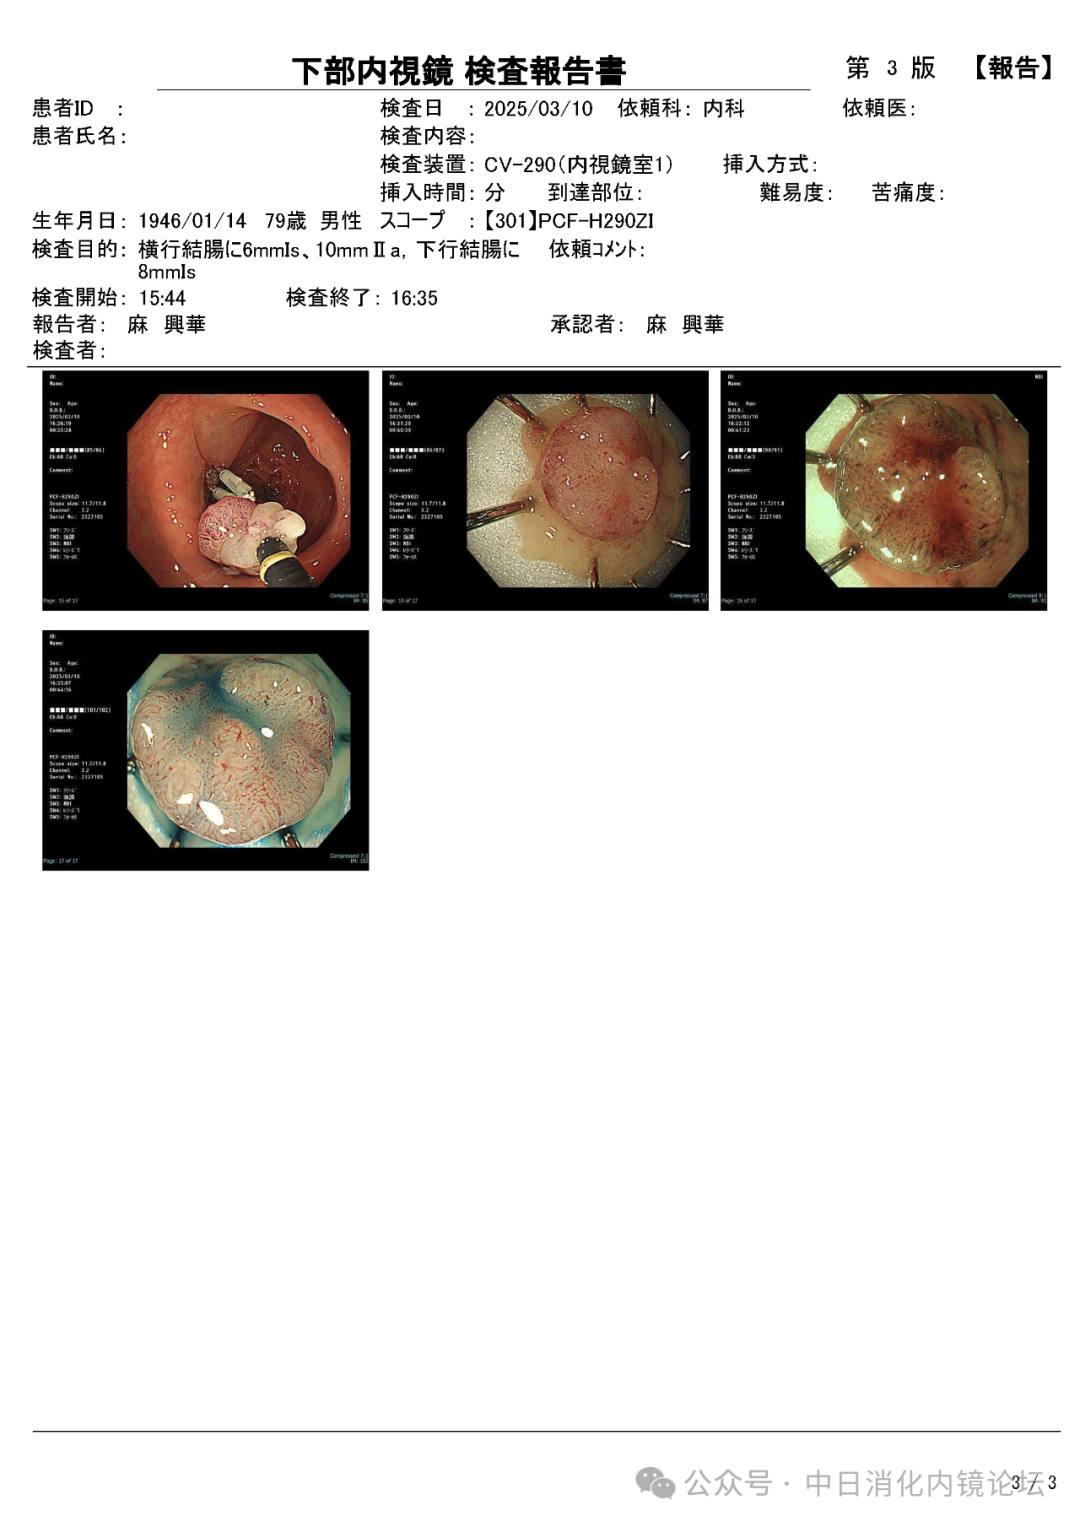

日本国立群马大学附属医院 麻兴华

在繁忙的临床工作中按照日本消化内镜学会倡导的病变观察流程,便可事半功倍,极大地提高诊断准确性和检查效率。病变观察远景→近景→放大,白光→NBIJNET→靛胭脂 pit pattern。切除后创面确认,确保无残留,断端阴性→肛侧腹侧点墨标记→标本固定,为病理诊断以及今后可能的追加治疗提供完整精确的原始资料。